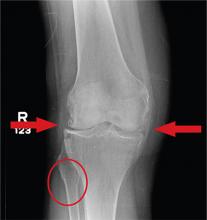

A 70-year-old woman presents to your emergency department for evaluation of right knee pain secondary to a fall. She and her husband, in the process of driving from Florida to their home in California, stopped for the night in your town. The patient states that shortly after getting up this morning, she tripped, lost her balance, and fell. All her weight landed on her right knee; she says it is now “extremely painful” to bear weight on that leg. She also twisted her right ankle, causing additional discomfort. Her medical history is significant for hypertension, which is controlled by medication. On physical exam, you note an elderly female who is uncomfortable but in no obvious distress. Inspection of her right knee shows no obvious deformity but a moderate amount of swelling. The patient has limited range of motion secondary to the swelling. She also has moderate tenderness circumferentially around the knee. There is additional swelling and mild bruising on both the medial and lateral aspects of the right ankle. You obtain a radiograph of the right knee. What is your impression?

The radiograph has several findings, one of which is a nondisplaced proximal fibula fracture. In addition, there is a moderate suprapatellar joint effusion. The patient also has fairly advanced tricompartment degenerative arthrosis. (To review, the tricompartment comprises all three anatomic areas of the knee: the patellofemoral, lateral tibiofemoral, and medial tibiofemoral joints.)

The patient was placed in a knee immobilizer, and orthopedic evaluation was coordinated .